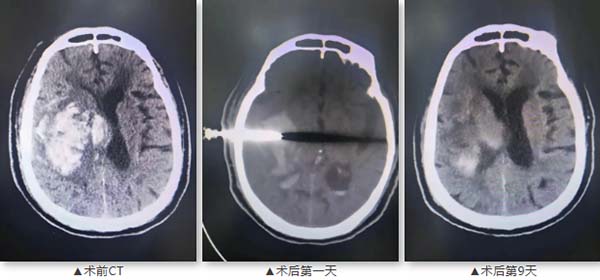

两名患者均为80岁以上高龄男性,分别因突发意识障碍入院。首例患者83岁,既往有高血压、多次脑梗死病史,长期口服阿司匹林,CT显示右侧基底节及丘脑大面积出血伴脑疝形成。第二例患者82岁,有20余年高血压、糖尿病史,曾行冠脉支架置入术,CT提示右侧额顶颞叶大面积脑出血。两名患者均病情危重,传统开颅手术风险极高。

第一例患者

首例患者于2025年9月15日接受手术,术后9天复查显示血肿基本清除;第二例患者于7月27日手术,术后10天血肿引流效果显著。两名患者术后病情均得到有效控制,生命得以挽救,稳定后转入社区医院进行康复治疗。患者家属对治疗效果表示满意,并赠送锦旗表达感谢。